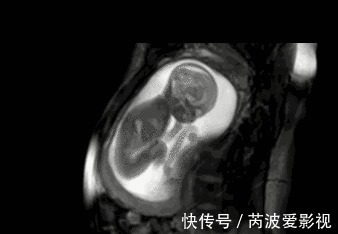

医生解释说:虽然宝宝现在很小,但有些聪明的宝宝确实可以神奇的与孕妈互动,听懂孕妈的话。而有的宝宝则不然,无论孕妈怎么样沟通安抚,都不会有互动的感觉,这类宝宝的智力相对于他们来说就一般。信号二、可以感受到孕妈的情绪在国外的一则新闻中曾报道过,通过实验证明,孕妈伤心流泪的时候,宝宝在腹中竟然也会跟着流泪,胎动会多一些;孕妈休息或心情舒缓时,宝宝相对安静一些。

文章插图

这些感知孕妈的反应都是胎儿与母体之间的互动,这种互动恰恰是宝宝感知力良好的一种表现,感知力良好的宝宝必定是聪明宝宝。这种感知比不只体现在孕妈的情绪上,当孕妈用手抚摸胎儿时,聪明的宝宝往往会感触到妈妈的抚摸,随之在抚摸的位置开始胎动。孕妈切记,每天摸孕肚的次数不宜过多,与宝宝互动的时候不要绕着肚子转,因为这样容易引起胎儿脐绕颈。